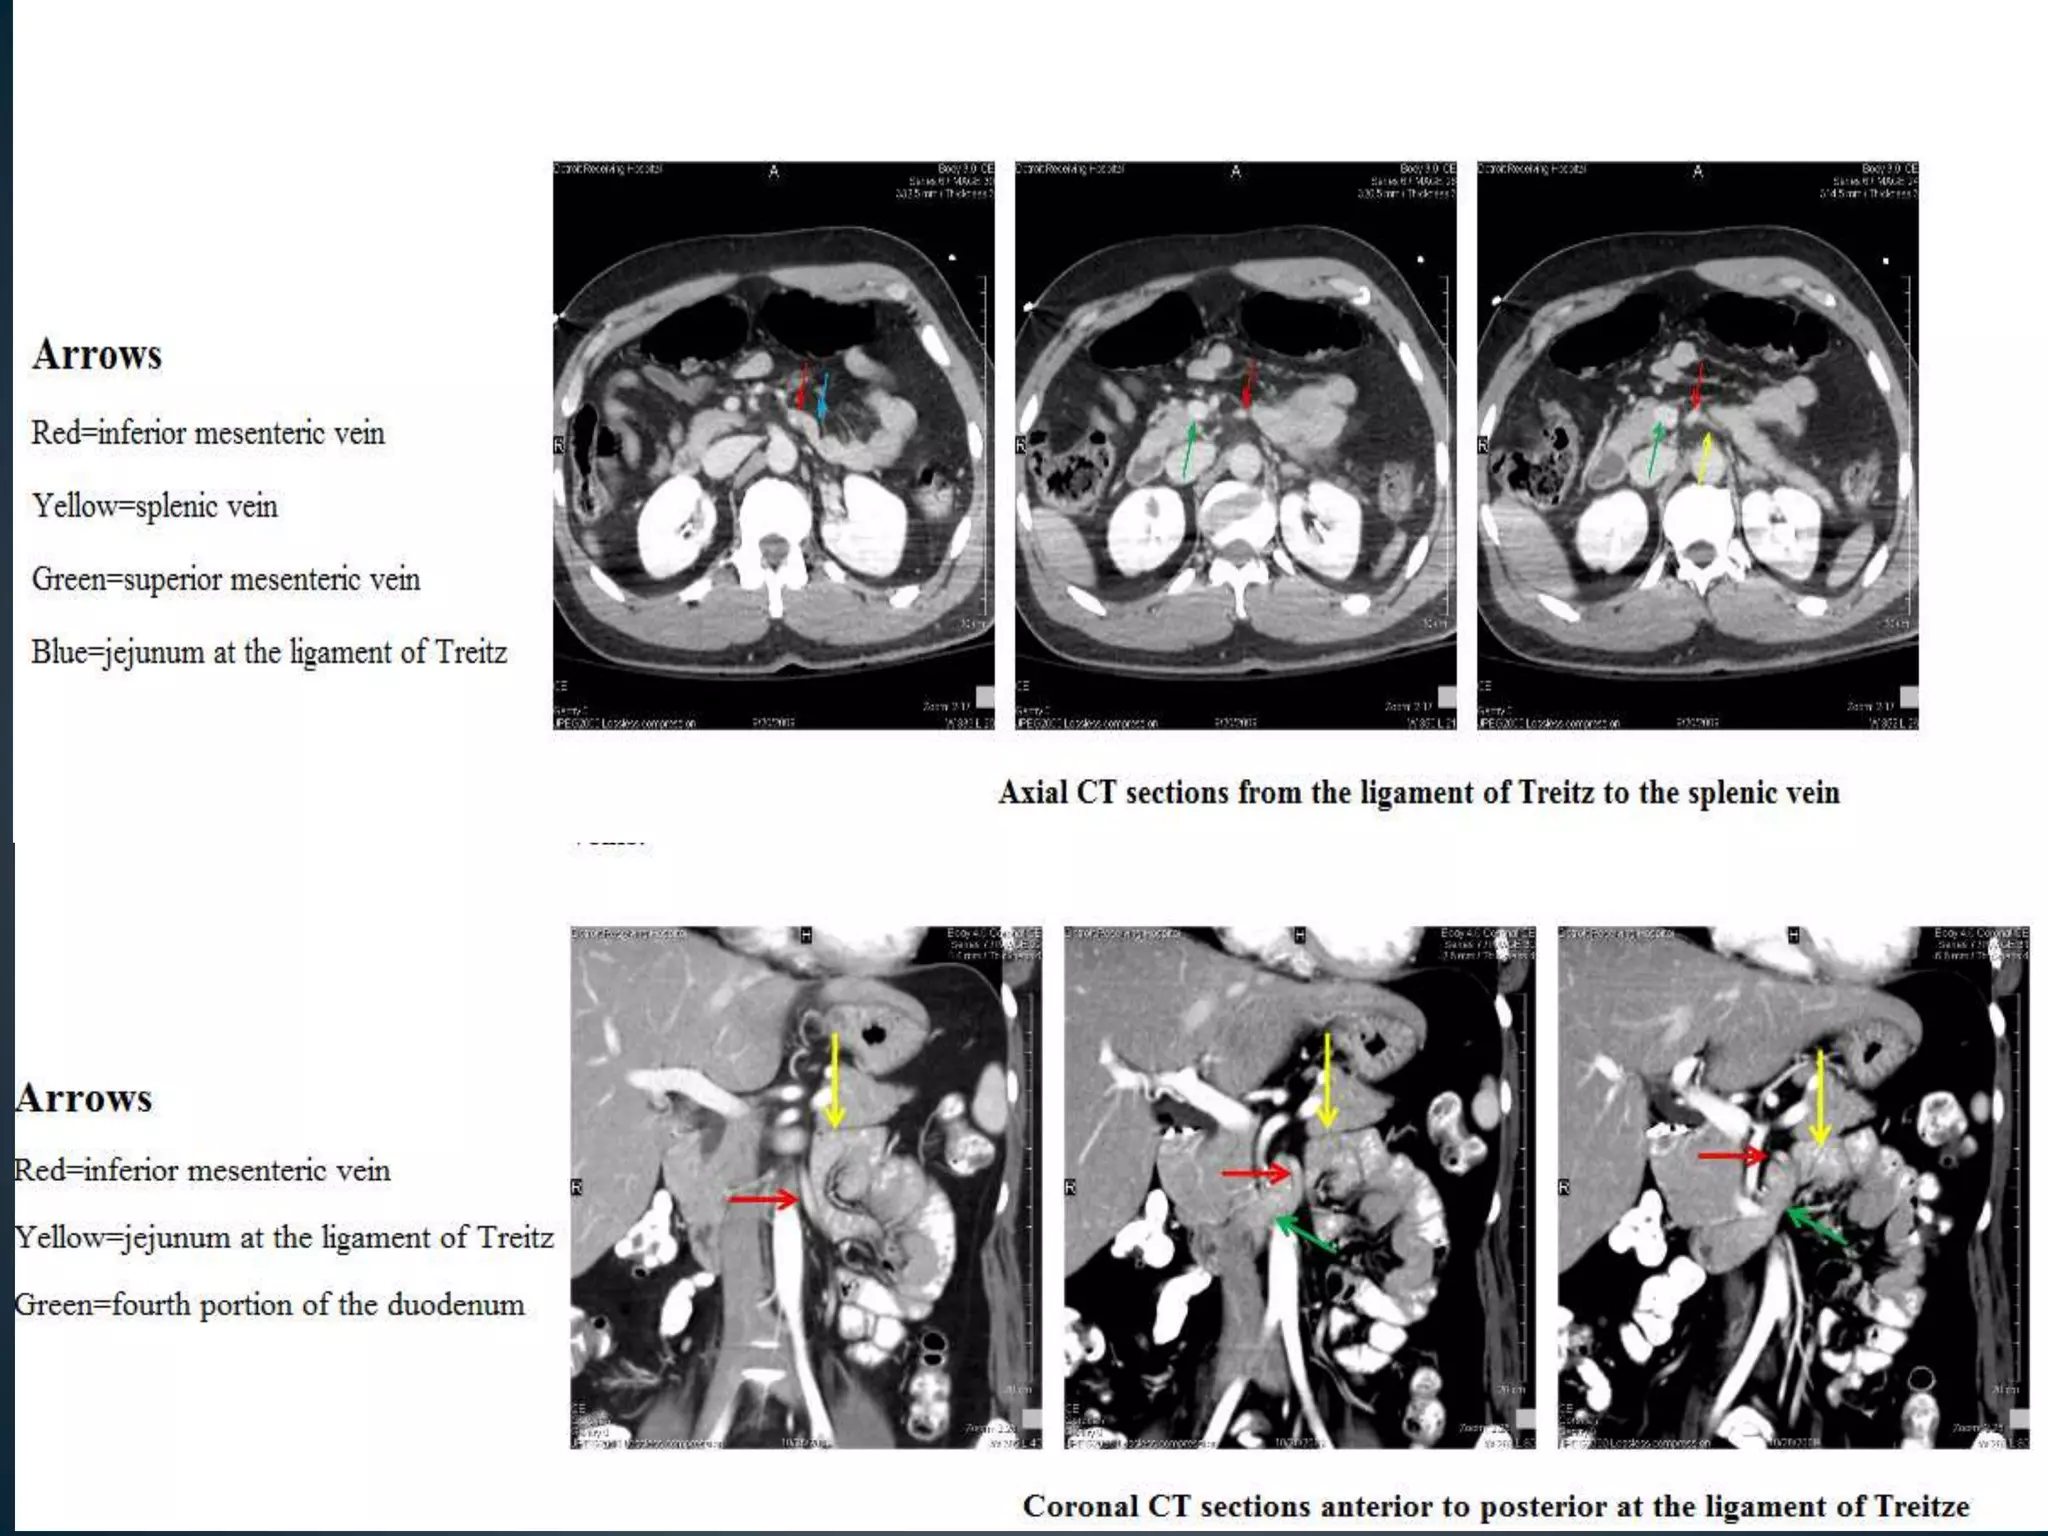

LIGAMENT OF TREITZ

• The celiac artery originates from the anterior surface of

the aorta at about the T12 level .

• The main trunk can take an upward, downward, or

forward course. Within 1 to 2 cm of its origin, it gives off

the left gastric artery and then divides into the common

hepatic and splenic artery

• The common hepatic artery runs toward the liver. After

giving off the gastroduodenal artery, it becomes the

proper hepatic artery and then divides into right and left

(and occasionally middle) hepatic arteries

• The middle hepatic artery supplies the quadrate lobe.

• The right gastric artery usually takes off from the

common or left hepatic artery but often is not visualized

at angiography. It supplies the pylorus and the lesser

curvature of the stomach and communicates with

distal branches of the left gastric artery.

• The cystic artery usually originates from the right hepatic

artery, although it may arise more proximally.

• The gastroduodenal artery runs between the neck of the

pancreas and the duodenum. Its first major branch

is the posterior superior pancreaticoduodenal artery.

• This vessel gives off branches to the pancreas on the left

and to the duodenum on the right.

• The gastroduodenal artery then divides into its terminal

branches, the anterior superior pancreaticoduodenal

artery and the right gastroepiploic artery

• The superior pancreaticoduodenal arteries lead into an

arterial network that supplies the head of the pancreas.

These vessels have rich anastomoses with the

corresponding branches of the inferior

pancreaticoduodenal artery, which originates from the

SMA

• The right gastroepiploic artery runs along the greater

curvature of the stomach and

• The SMA supplies the bowel from the distal duodenum to

the mid-transverse colon It originates from the

anterior surface of the aorta at about the L1-L2

level, approximately 1 to 2 cm below the celiac trunk.

The SMA runs behind the body of the pancreas and

then enters the root of the mesentery.

• The IMA supplies the colon from its mid-transverse

segment to the rectum . It originates from the left

anterolateral surface of the aorta at about the L3-L4

level.

• The vessel runs inferiorly for several centimeters and

then gives off the left colic artery.